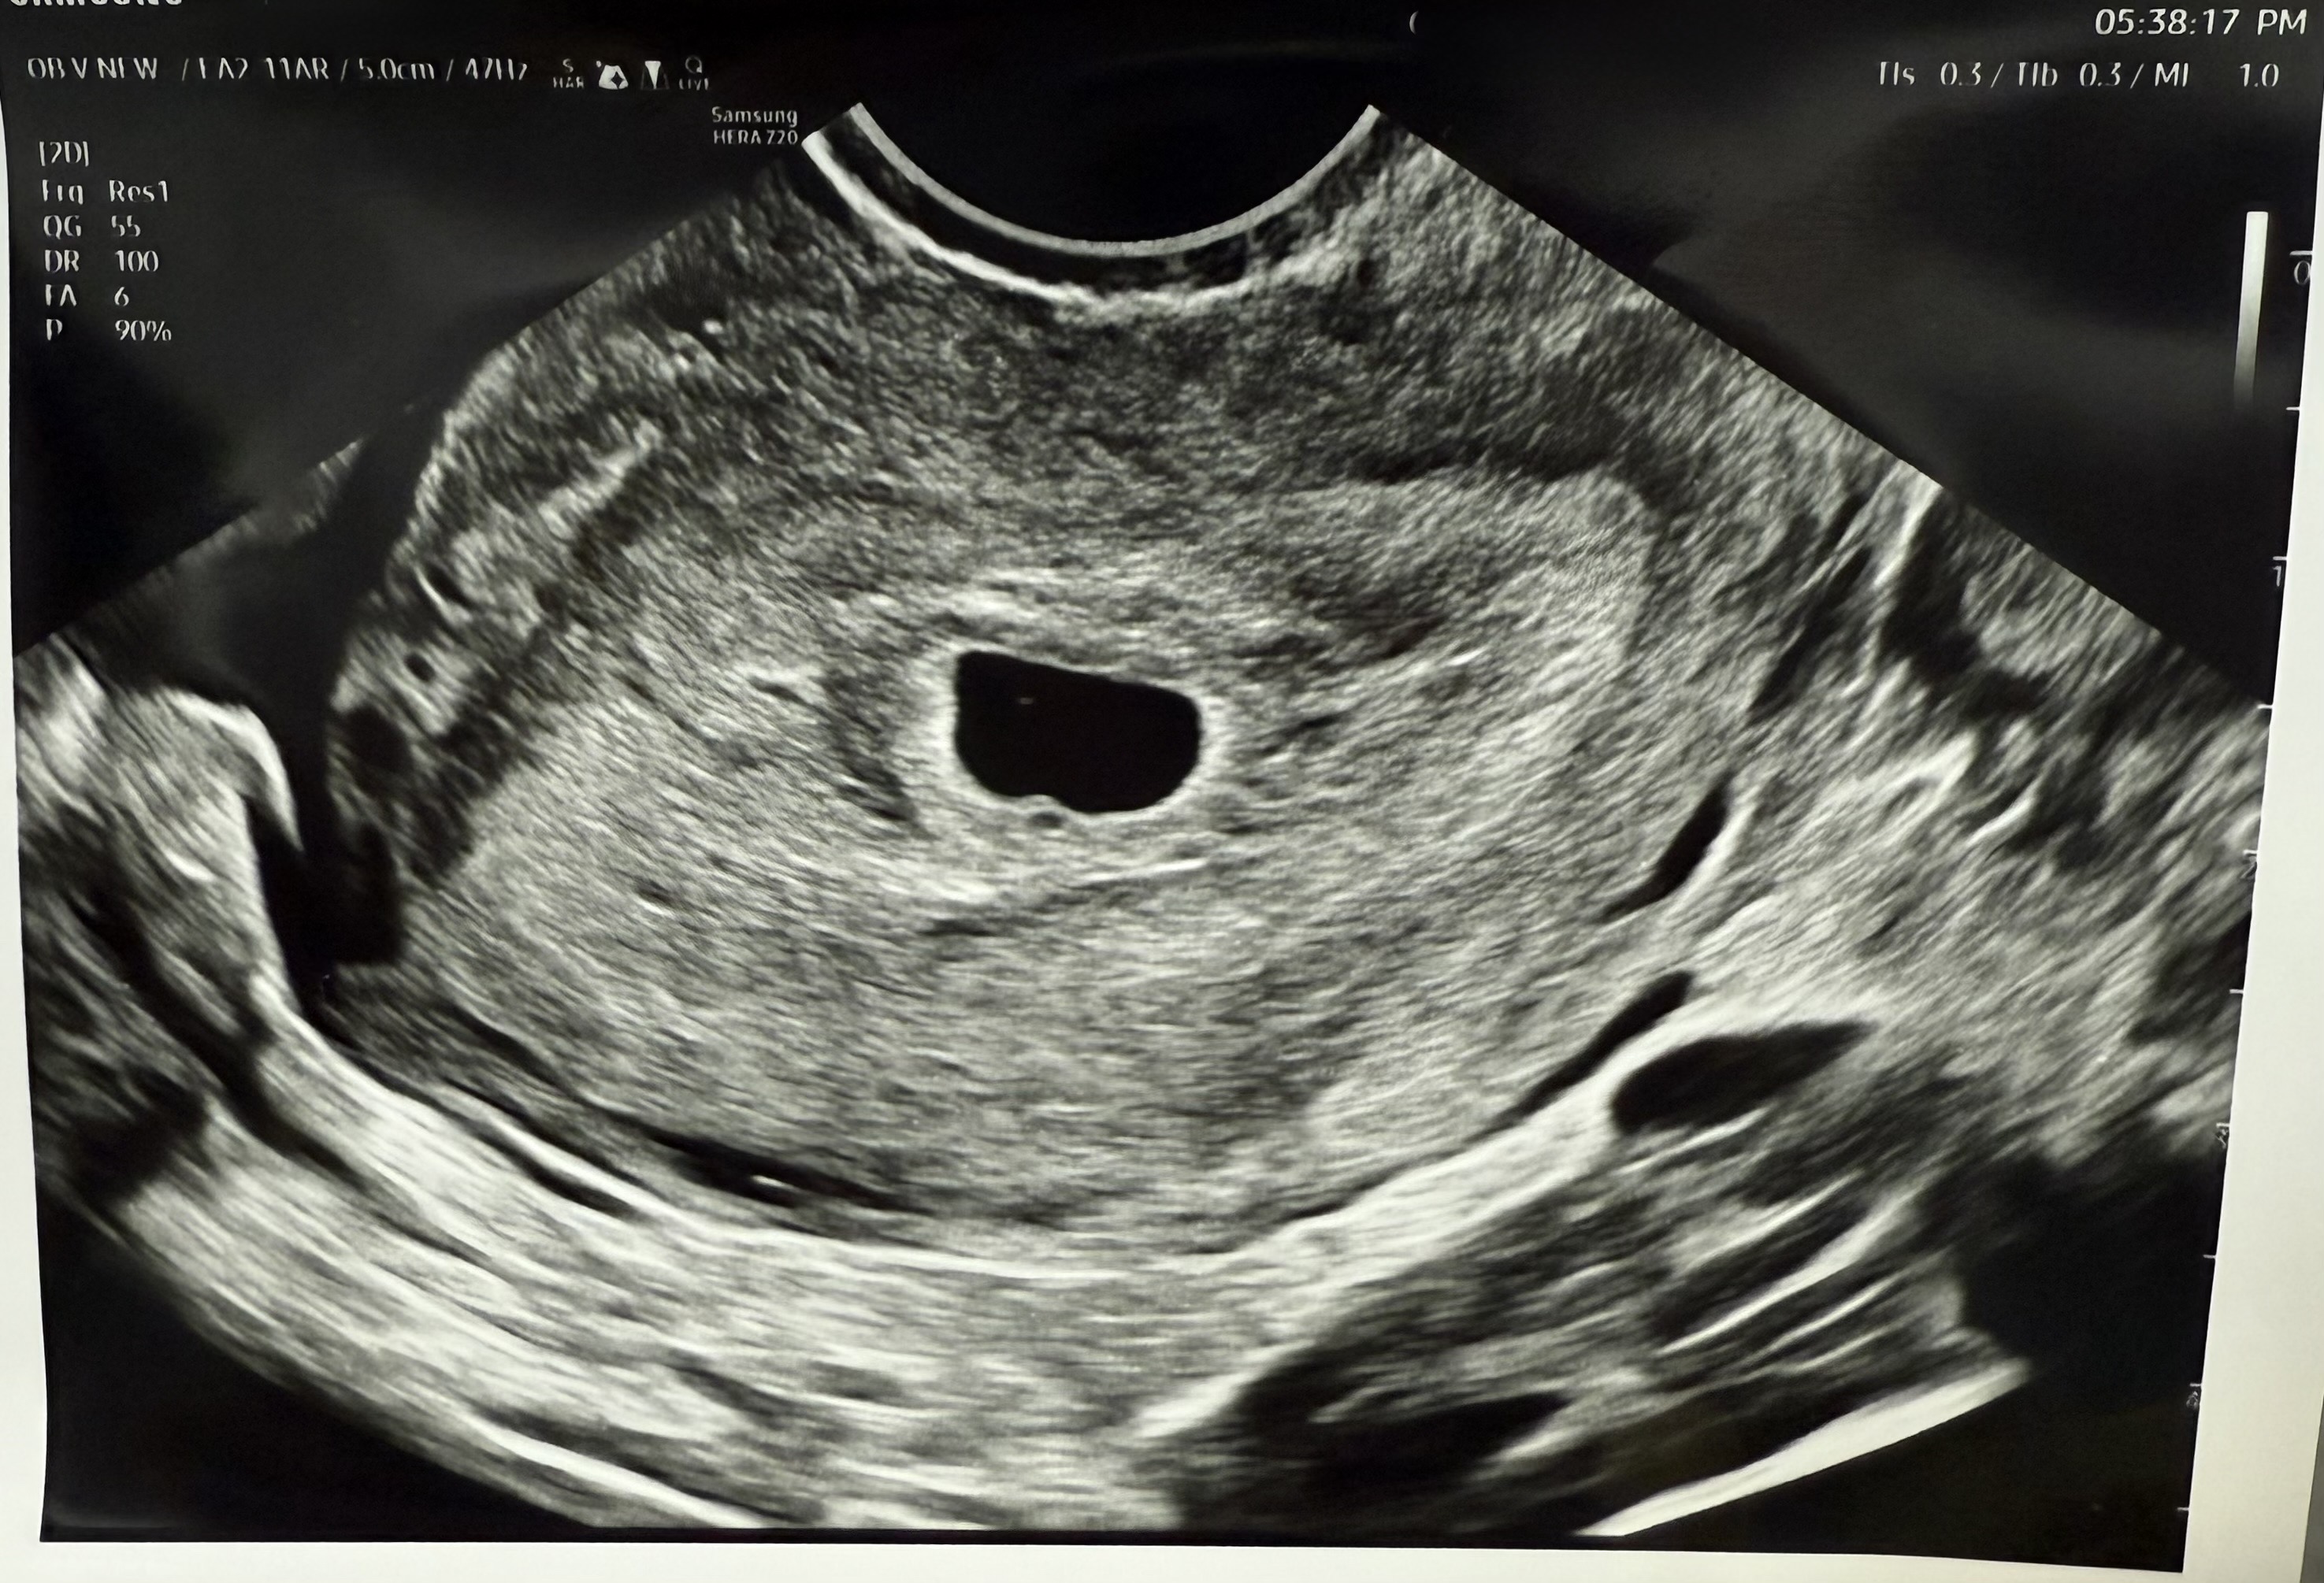

4주6일차

이 전에 자궁외 임신 판정을 받아 마음 고생을 많이 했다가 드디어 어렵게 자연임신에 성공 하였습니다 원래 예민한 편이라 그 날따라 이상하게 임테기를 해보고싶어 테스트 하였는데 양성나와 병원에 연락하여 4주 6일차에 초음파 보고왔습니다 그런데 의사쌤께서 주수를 착각하신건지 난황이 안보인다고 하시는데… 원래 안보이는거 맞을까요..?ㅠㅠ 그리고 4주6일차에 비해 애기집이 너무 커보여서 그러는데.. 정상 맞을까요..?? 조언 부탁드립니다..ㅠㅠ - 그리고 현재 5주3일차인데 가끔씩 아침 공복에 속이 안좋았다가 또 어느날은 좋았다가 반복합니다 이것도 정상 맞을까요?ㅜㅜ 자궁외임신 후 첫 임신이라 너무 조심스러워지고 이만저만 걱정이 많습니다ㅜㅠ 긴 글 읽어주셔서 감사합니다

4주6일에 난황이 보이는 산모보다 안 보이는 산모가 훨씬 많아요 아기집 크기는 측정값이 없어 잘 모르겠지만 잘 성장해가면 좋은거죠ㅎㅎ 그리고 입덧은 왔다갔다하니 속이 좋은 날은 감사해하시면 돼요 임신 축하드려요^-^